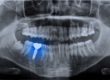

Adult orthodontic services, or braces, help improve the smile using one or several devices placed into the mouth or on the teeth shift the teeth into the proper position. It can take some time to do this, but this gentle process can correct many of the problems people have with teeth straightening. These solutions, including braces and dental aligners, are very safe to use, and they work for adults much in the same way as they do for teens.

If you have any of these concerns, adult orthodontic services may be able to correct them using a non-invasive application. This type of tray aligner or bracing technology can help to slowly move the teeth into a more desirable position, improving overall smiles every day. When you meet with an orthodontist, you will be able to get more insight into how much improvement you can have. The first step is to discuss your options and determine if this can work for your needs.